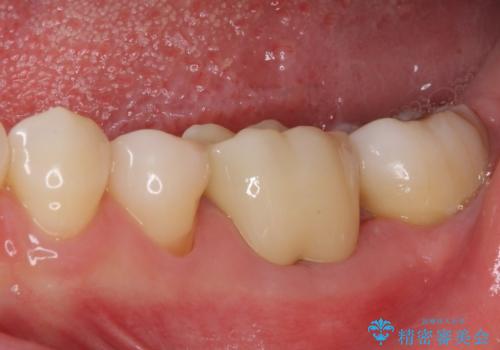

術後6ヶ月でレントゲン写真を撮影したところ、出血の原因であった穴付近の溶けていた骨が回復している様子が認められました。